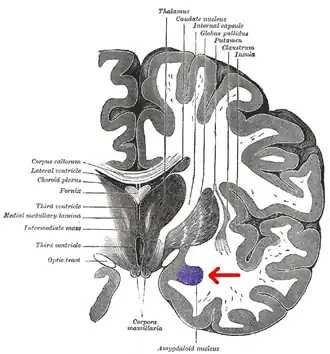

Coronal section of brain through intermediate mass of third ventricle. Amygdala is shown in purple. | |